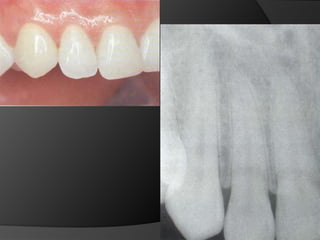

El análisis para seleccionar la ubicación de la línea de terminación se enfoca en 2 componentes:Estética vs HigieneExtensión mínima dentro del surco gingivalDisimular la zona de asentamientoFacilitar la higiene del pacienteNecesidad de aumentar la retención y estabilidadLínea de Sonrisa

PRINCIPIOS ESTÉTICOSRestauraciones con forma, contorno y color adecuados

CORONA TOTALMENTE CERÁMICA: Combinación de recubrimiento completo y máxima estética. La eliminación de estructura dentaria es mayor.

CARILLAS EN CERÁMICA: Alternativa menos agresiva cuando lo que se busca es el cambio de color o de forma en la superficie vestibular